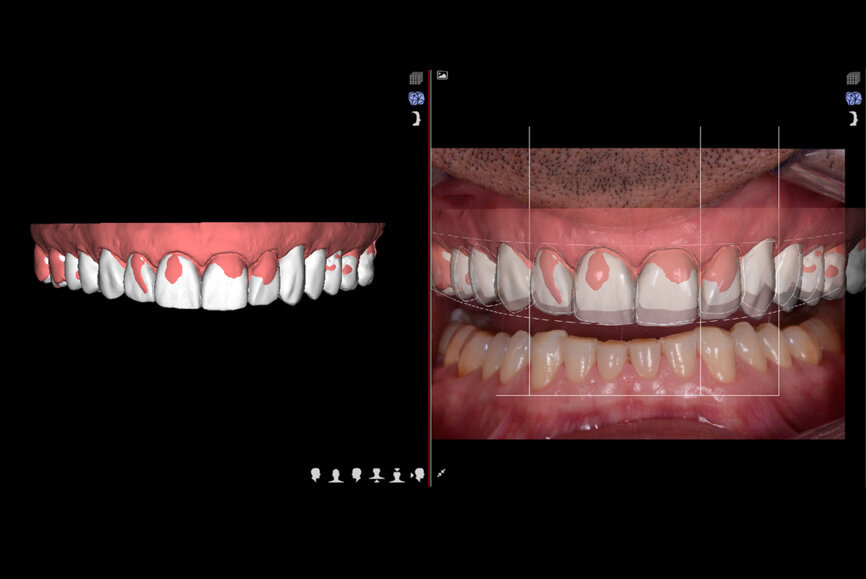

The old tooth preparations in the second sextant were retained. The maxillary posterior teeth (#14–17 and 24–27) and the mandibular posterior teeth (#34–37 and 44–47) were not prepared, and the mandibular anterior teeth were minimally prepared. A new intra-oral scan was produced. The information was transmitted to the DSD laboratory (Fig. 9), which created an STL file with virtual models produced in the laboratory (Anatomic Lab). These 3D models (V-Print model, VOCO) were created in a 3D printer (SolFlex 650, VOCO).

Fig. 10: Final veneers and crowns digitally prepared using the Ceramill Mind design software and produced in a milling machine (Ceramill

Motion 2) from machinable lithium disilicate ceramic blocks (VITABLOCS TriLuxe forte).